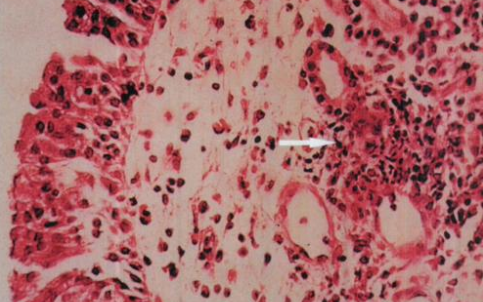

肉芽肿的主要细胞成分是上皮样细胞和多核巨细胞。

肉芽肿的本质是迟发超敏反应所致的炎症,免疫应答中起作用的主要是巨噬细胞和上皮样细胞。因此肉芽肿可定义为巨噬细胞及其衍生细胞(如上皮样细胞,多核巨细胞)的聚集,伴随或不伴随其他炎症细胞的出现。

肉芽肿内的多核巨细胞由上皮样细胞融合而来,其胞体巨大(40~50μm)胞浆丰富、嗜酸,胞核数十至数百不等。据其胞核分布特点,可将多核巨细胞分为规则型和杂乱型两大类。

由局部组织细胞的炎症增生形成的境界明显的结节状病灶。其主要成分通常为具有很强吞噬作用的巨噬细胞,这些细胞以后可以演变成为体积大、多边形、胞浆丰富,有时含有大量类脂的所谓类上皮细胞,还可演变为多核巨细胞。由于病原因子的不同,肉芽肿的形态结构多具有一定的特异性。肉芽肿可分为两大类,即感染性肉芽肿和异物肉芽肿。 在病理切片上,“肉芽肿”有特有的形态学改变——以小叶为中心的肉芽肿和慢性、亚急性炎症,炎性细胞是以淋巴细胞、巨噬细胞、上皮样细胞浸润为主。虽然为慢性炎症过程,但常突然急性发作,炎性肿块短期内迅速增大,形成脓肿、坏死、窦道或溃疡。 炎症肉芽肿inflammatory granuloma 又称肉芽肿性炎。巨噬细胞增生而形成境界明显的结节状病灶。主要成分为具有很强吞噬作用的巨噬细胞。一般分为感染性肉芽肿和异物性肉芽肿,前者由生物病原引起,后者由异物引起。肉芽肿形态结构多具一定的特殊性,如结核杆菌引起的结核性肉芽肿,麻风杆菌引起的麻风肉芽肿以及霉菌引起的各种霉菌性肉芽肿等。